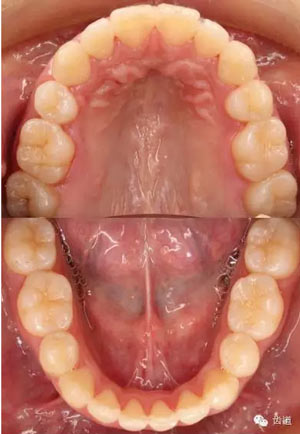

矯治結(jié)束后口內(nèi)像

治療后模型

治療前后口內(nèi)相對(duì)比

橫向不調(diào):牙弓寬度輕度不調(diào)的解決在于上頜適當(dāng)?shù)臄U(kuò)弓與后退左上牙列,以及下頜適當(dāng)?shù)目s弓與下磨牙前移,矯治后上頜磨牙寬度由41.8mm變?yōu)?3.1mm,下頜磨牙寬度由39.6mm變?yōu)?7.8mm。